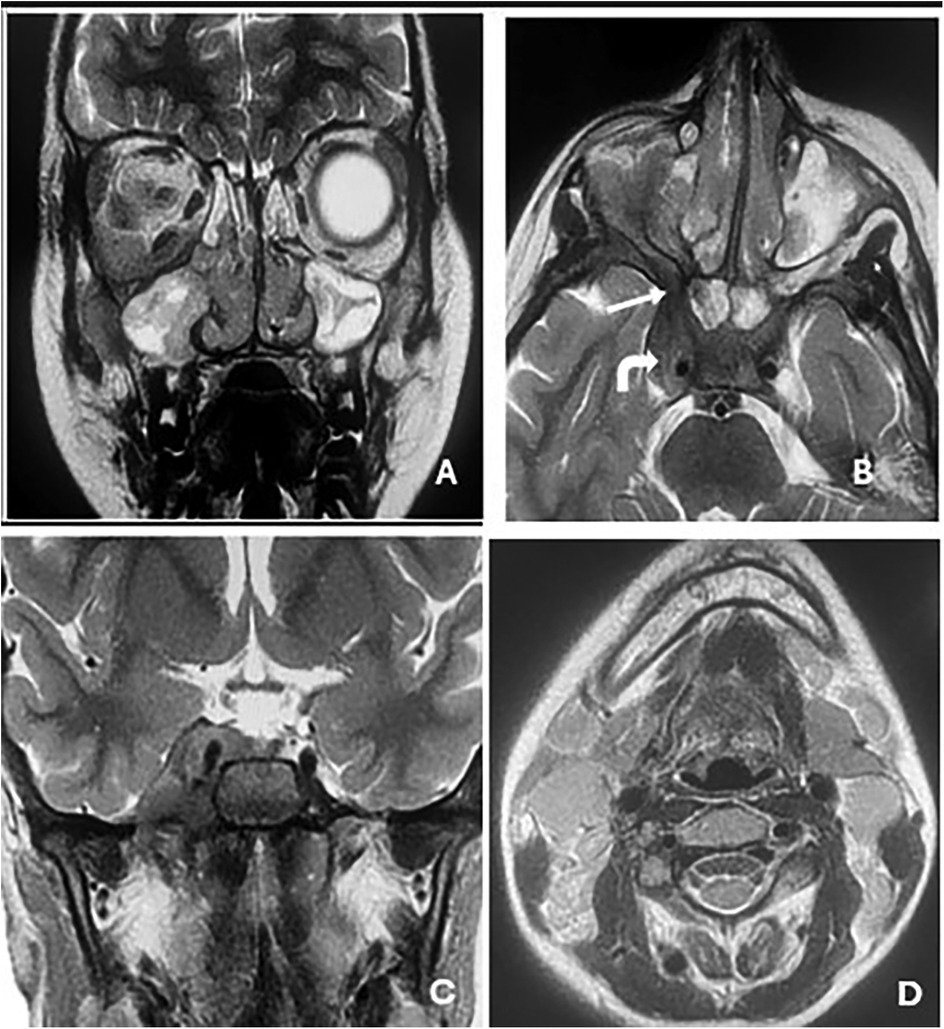

Background : Cavernous sinus tuberculosis is an extremely rare manifestation of central nervous system tuberculosis in children, with only two cases reported worldwide. It can mimic malignancy or other inflammatory conditions. Its occurrence in children with primary immunodeficiency, particularly major histocompatibility complex (MHC) class II deficiency, has not yet been described. Case report : We report an 11-year-old girl with a history of recurrent infections and chronic otitis media. She presented with right orbital swelling, severe headaches, and exophthalmos. Imaging revealed an extensive mass in the sinonasal and orbital regions, extending to the skull base and cavernous sinus. Computed tomography–guided biopsy and histopathology, supported by PCR testing for Mycobacterium tuberculosis, confirmed extensive orbital and cervicofacial tuberculosis. Immunological evaluation and genetic analysis revealed familial MHC class II deficiency. The patient received antituberculous therapy (HRZE followed by HR), leading to clinical and radiologic improvement. She continues intravenous immunoglobulin replacement every 21 days while awaiting bone marrow transplantation. Conclusions : This case highlights the importance of considering tuberculosis in atypical cavernous sinus lesions in children, especially in endemic regions. Severe or unusual infections should prompt evaluation for underlying immunodeficiency.